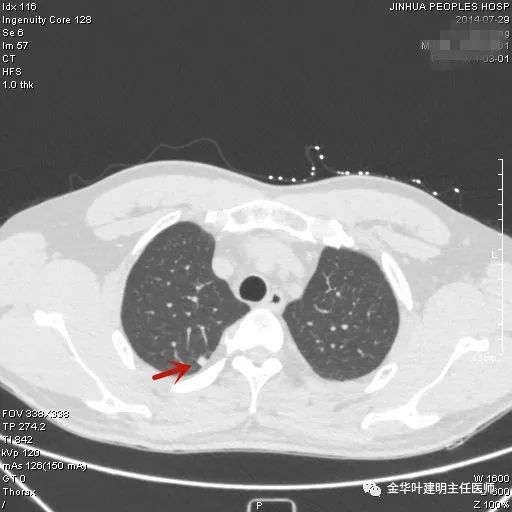

上图是肺内淋巴结。但我们看有明显血管进入病灶,胸膜似有牵拉,恶性的特征也不少。